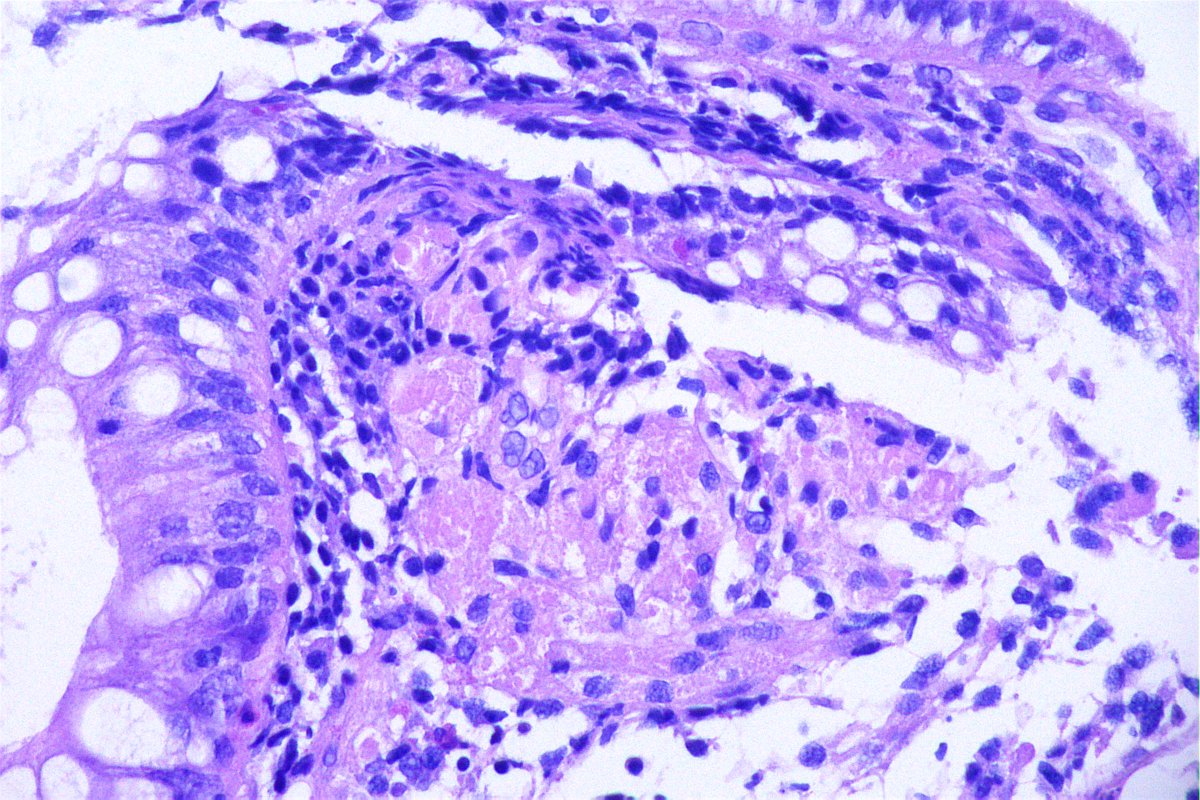

@GeronimoJrLapac

Ger么nimo Jr.

2 months

F, 47yo. The clinical information is: subepithelial lesion in the ileocecal valve. #gipath